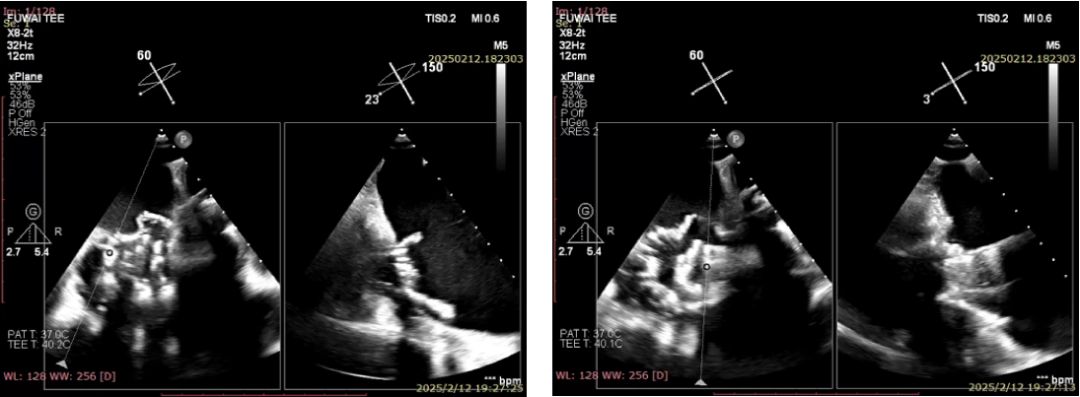

术后即刻

术后即刻超声可见三尖瓣返流消失